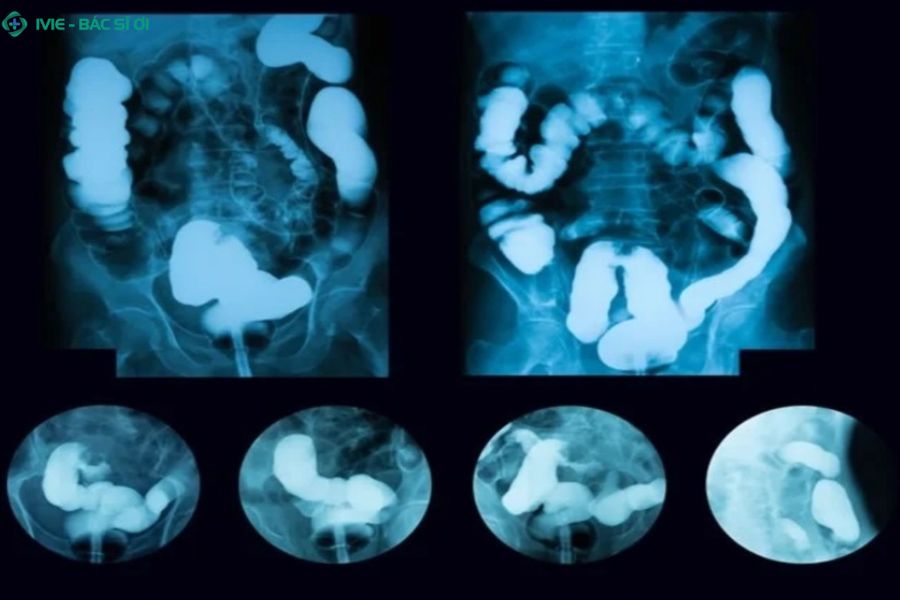

Chụp X-quang tiêu hóa

Phương pháp này sử dụng thuốc cản quang baryt để thấy hình ảnh dạ dày - thực quản qua phim X-quang. Dùng để phát hiện bất thường hình thái, hẹp thực quản, thoát vị hoành. Tuy nhiên, không đánh giá được mức độ viêm hay biến chứng vi thể.